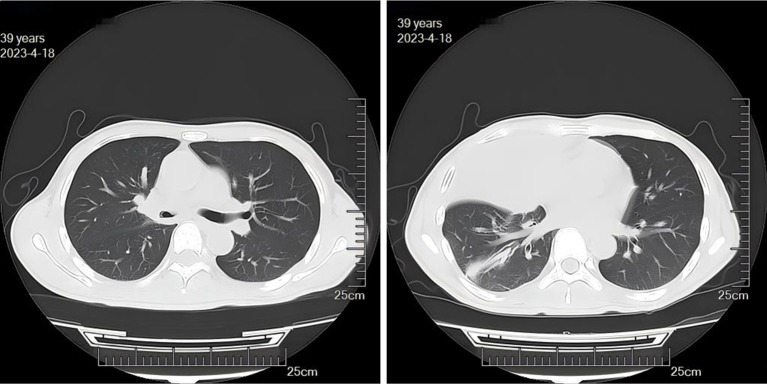

Case description: A 39-year-old male patient was diagnosed with PM and complicated by bronchial obstruction. Although surgical debridement of mucormycosis and antifungal therapy are generally preferred treatment, our patient presented with a high burden of invasive disease and was deemed ineligible for surgery. We therefore had to compromise and palliate his bronchial obstruction with a bronchial stent while continuing intravenous, nebulized, and bronchoscopically applied antifungals. The intervention markedly alleviated the patient's symptoms of chest tightness and dyspnea. However, given the advanced stage at presentation, the prognosis was already poor. Despite these measures, the aggressive underlying infection continued to progress, ultimately leading to erosion into a major vessel and catastrophic hemoptysis.

Conclusions: The implantation of bronchial stents in patients with PM can effectively alleviate severe bronchial obstruction caused by mucormycosis infection, improve pus drainage, and promote infection resolution. However, as a complete surgical resection of the lesion was not performed, the patient remains at risk of potentially catastrophic hemoptysis due to the possibility of pulmonary vascular invasion by mucormycosis. The potential increase in hemoptysis risk associated with stent implantation warrants further investigation.